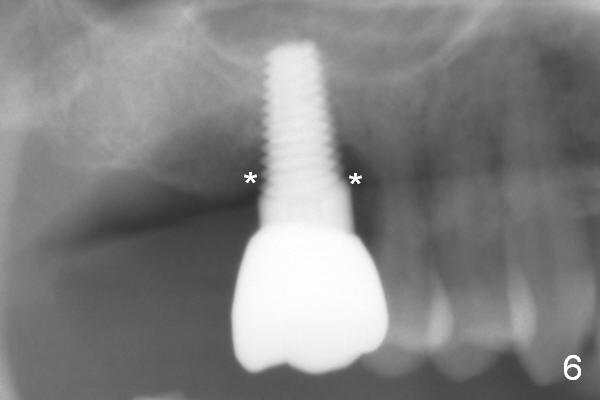

The patient returns asymptomatic for follow up 1 year post cementation. In fact the buccal threads are exposed without infection (Fig.5 <). There remains bone loss around the most coronal threads (Fig.6 *). Water pik is recommended.